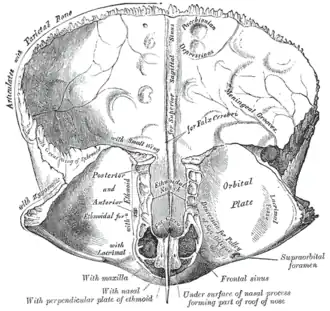

Frontal bone. Inner surface. (The Pars orbitalis is the bottom third.) | |

The orbital or horizontal part of the frontal bone (pars orbitalis) consists of two thin triangular plates, the orbital plates, which form the vaults of the orbits, and are separated from one another by a median gap, the ethmoidal notch.

- The ethmoidal notch separates the two orbital plates; it is quadrilateral, and filled, in the articulated skull, by the cribriform plate of the ethmoid.

- The margins of the notch present several half-cells which, when united with corresponding half-cells on the upper surface of the ethmoid, complete the ethmoidal air cells.

- Two grooves cross these edges transversely; they are converted into the anterior and posterior ethmoidal canals by the ethmoid, and open on the medial wall of the orbit.

- The anterior canal transmits the nasociliary nerve and anterior ethmoidal vessels,

- the posterior, the posterior ethmoidal nerve and vessels.

- The ethmoidal notch separates the two orbital plates; it is quadrilateral, and filled, in the articulated skull, by the cribriform plate of the ethmoid.

- In front of the ethmoidal notch, on either side of the frontal spine, are the openings of the frontal air sinuses.

- These are two irregular cavities, which extend backward, upward, and lateralward for a variable distance between the two tables of the skull; they are separated from one another by a thin bony septum, which often deviates to one or other side, with the result that the sinuses are rarely symmetrical.

- Absent at birth, they are usually fairly well-developed between the seventh and eighth years, but only reach their full size after puberty.

- They vary in size in different persons, and are larger in men than in women.

- They are lined by mucous membrane, and each communicates with the corresponding nasal cavity by means of a passage called the frontonasal duct.